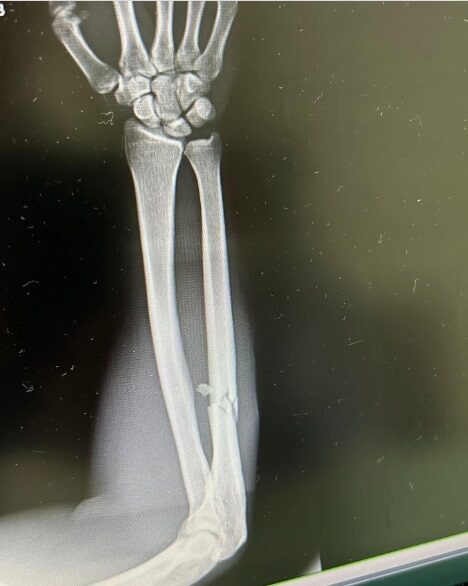

ซ้ายหนักจริง ดาวิต คิเรีย คู่ชก ตะวันฉาย โพสต์ภาพฟิลม์เอกซเรย์ โดนเตะจนแขนหัก เศร้า ร่างกายกำลังดี แต่ต้องมามีอาการบาดเจ็บครั้งใหญ่

หลังชก ดาวิต คิเรีย โพสต์ข้อความผ่านทางอินสตาแกรมdavitkiria โดยเป็นภาพฟิลม์เอกซเรย์ กระดูกแขนหัก พร้อมเขียนข้อความบรรยาย ระบุว่า ฉันอยู่ในรูปร่างที่ดีมาก สิ่งเดียวที่จะหยุดฉันได้คือบาดเจ็บใหญ่หรือโดนน็อก น่าเศร้าที่มันเกิดขึ้น!!!